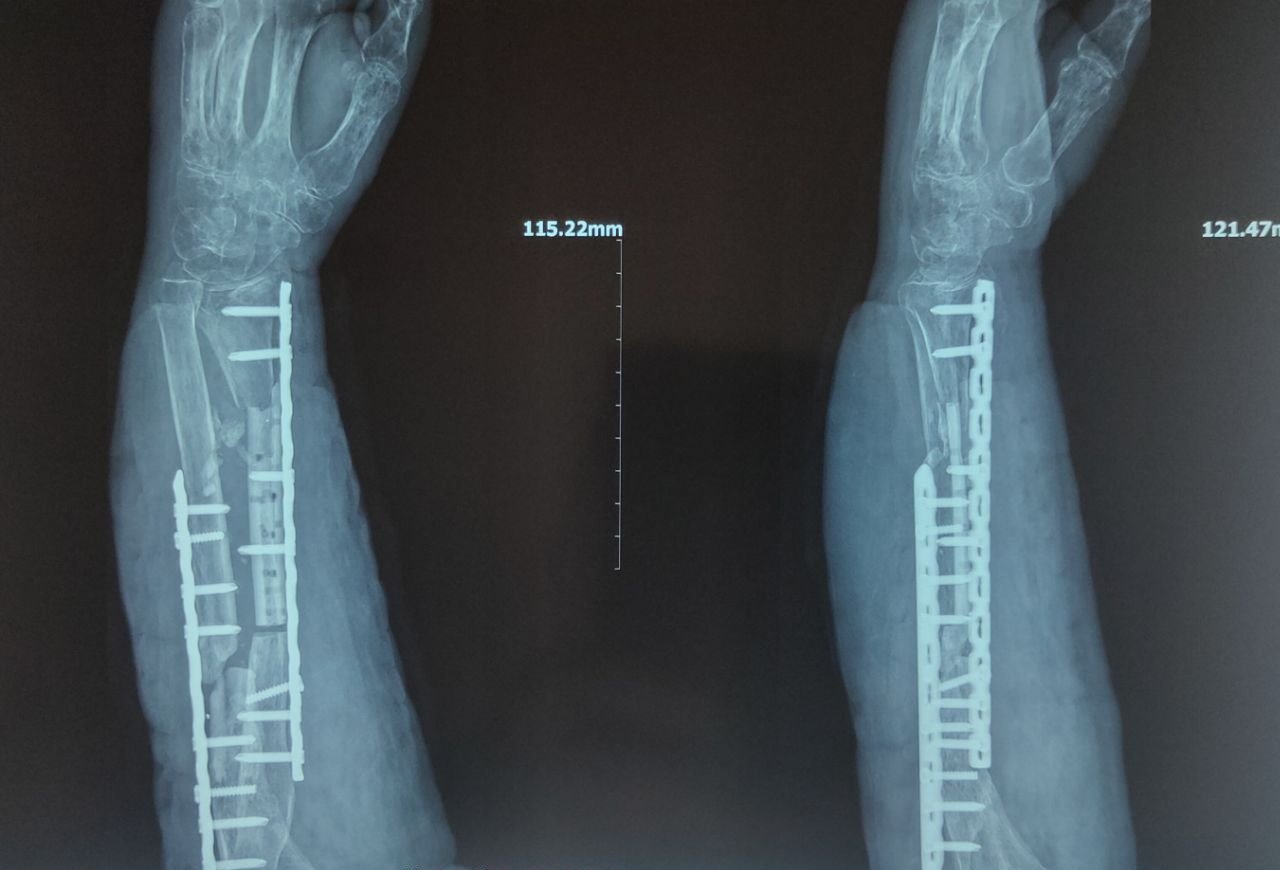

Під час проведення операції лікарі вперше одночасно застосували технології індивідуального 3D-моделювання, 3D-друку та алоостеопластики — під індивідуальні параметри пацієнта виготовили пластину для остеосинтезу, а пошкоджені фрагменти, які не підлягали відновленню, замінили штучним матеріалом.

За даними медиків, пацієнтові 50+ років, він отримав вогнепальне поранення передпліччя, багатоуламковий перелом обох кісток передпліччя та дефект променевої кістки до 10 см.

— Лікували поетапно і було необхідно дочекатись повного загоєння ран. У нашій лікарні провели КТ-обстеження і передали дані, на основі яких наші партнери підібрали індивідуальний анатомо-функціональний алоостеотрансплантат променевої кістки, а також змоделювали і виготовили індивідуальну друковану 3D-модель ушкодженого сегмента та індивідуальну 3D радіальну пластину для виконання таргетованого остеосинтезу, — говорить лікар.